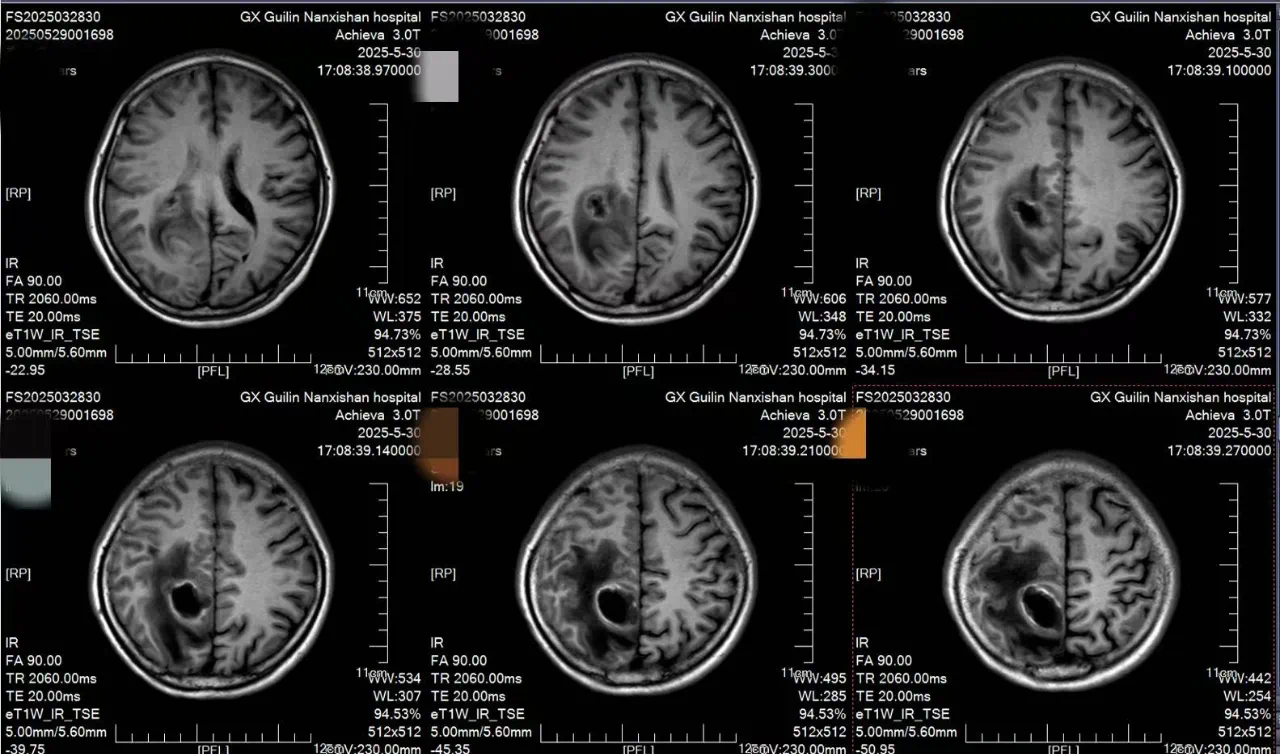

患者李女士自诉约2天前无明显诱因出现头痛,疼痛性质为阵发性胀痛,可自行缓解,伴有左侧肢体乏力,行走不稳。在本地医院检查后诊断:右侧顶叶占位性病变并周围脑组织水肿。为进一步治疗,来到南溪山医院就诊,完善各项检查后确诊为:功能区脑脓肿。

面对李女士的病情,神经外科团队经过反复讨论,决定采用机器人辅助实时可视化抽吸微创手术。手术前,团队通过3D影像重建技术,为李女士的脑部构建了精准的三维模型,清晰标注出脓肿的大小、形态以及与周围血管、神经的位置关系。手术机器人则根据这些数据,自动规划出最优穿刺路径,误差可控制在0.5毫米以内。

在机器人“导航”系统的引导下,神经外科主任王文波主任医师手持穿刺针,沿着预设路径稳步推进。术中,实时影像系统如同“透视眼”,清晰显示穿刺针的位置和脓肿内部情况,医生可以动态观察抽吸过程,确保每一步操作都精准无误。传统开颅手术需要打开十几厘米的切口,创伤大、恢复慢,还可能引发感染。而机器人辅助手术不仅创伤小,还能最大限度减少对正常脑组织的干扰。术后李女士肢体功能逐渐恢复,一周后完全恢复。